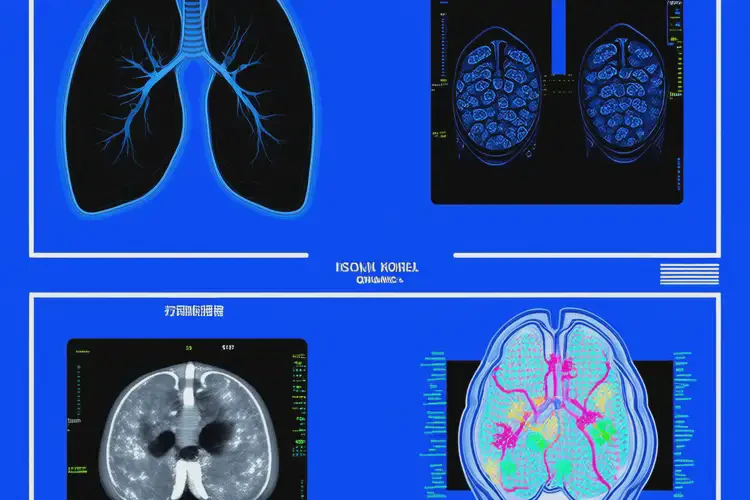

深圳影像科醫(yī)院是集醫(yī)學(xué)影像診斷、科研與教學(xué)于一體的現(xiàn)代化醫(yī)療機(jī)構(gòu),專注于通過先進(jìn)的影像技術(shù)為患者提供精準(zhǔn)的疾病篩查與診斷服務(wù)。該機(jī)構(gòu)配備高場強(qiáng)磁共振(MRI)、64排以上螺旋CT、數(shù)字化X線攝影(DR)及超聲等設(shè)備,由資深影像科醫(yī)師團(tuán)隊(duì)進(jìn)行專業(yè)解讀,確保檢查結(jié)果的準(zhǔn)確性與及時(shí)性,廣泛應(yīng)用于腫瘤、心腦血管病、骨關(guān)節(jié)疾病及早期健康篩查等領(lǐng)域。

現(xiàn)代醫(yī)學(xué)影像學(xué)已發(fā)展出多種核心技術(shù),每種技術(shù)基于不同的物理原理,適用于不同的臨床場景。選擇合適的影像技術(shù)對(duì)于提高診斷效率、減少誤診漏診至關(guān)重要。

CT通過多角度X線掃描并經(jīng)計(jì)算機(jī)重建,生成橫斷面圖像,具有較高的空間分辨率。適用于急性創(chuàng)傷、腦出血、肺部結(jié)節(jié)、腹部臟器病變等的精細(xì)評(píng)估。

MRI利用強(qiáng)磁場和射頻脈沖,檢測人體內(nèi)氫原子的信號(hào)變化,對(duì)軟組織分辨率極高。廣泛用于腦部疾?。ㄈ缒X梗死、腫瘤)、脊柱病變、關(guān)節(jié)軟骨損傷及婦科疾病的診斷。